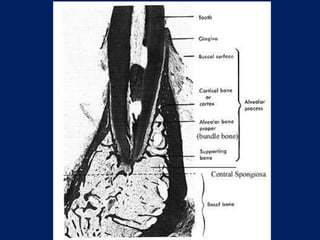

ALVEOLAR

BONE

PROPER

LAMELLATED

BUNDLE

SUPPORTING

CORTICAL

PLATE

SPONGY

SUPPORTING ALVEOLAR BONE

• It consists of two parts –

 Cortical plates (Outer and inner)

 Spongy bone

Cortical plates: these are made up of

compact bone & form the outer and

inner plates of alveolar bone.

Cortical bone varies in thickness in

different areas – it is thicker in the

mandible than in the maxilla and

thicker in the premolar-molar

region than in the anteriors.

STRUCTURE OF ALVEOLARBONE ALVEOLAR BONE ALVEOLAR BONE PROPER LAMELLATED BONE BUNDLE BONE SUPPORTING ALVEOLAR BONE CORTICAL PLATE SPONGY BONE